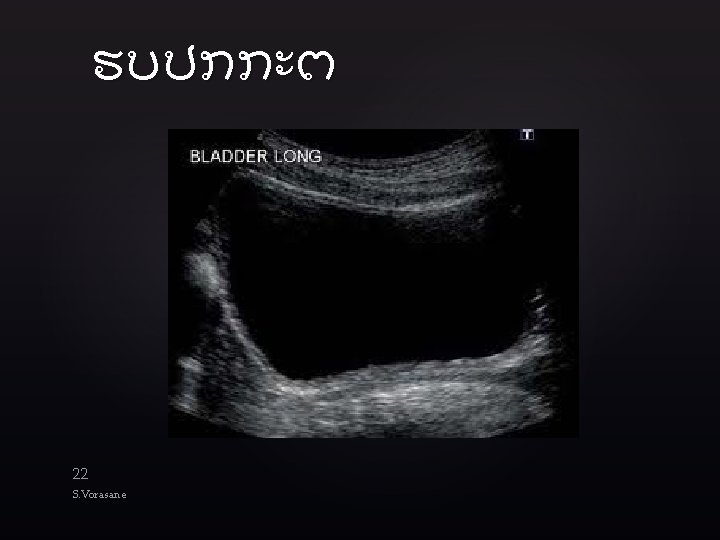

ທອງນອຍ 21 S. Vorasane